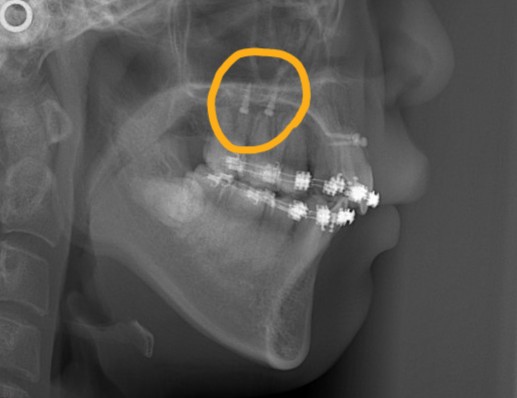

レントゲン写真を確認すると、

この患者さんの場合、

*歯並びの写真で見ると「出っ歯」であるとは分かり難いですが、頭部全体のレントゲン写真を見ると、出っ歯であることがハッキリと分かります。

レントゲン写真で確認すると、